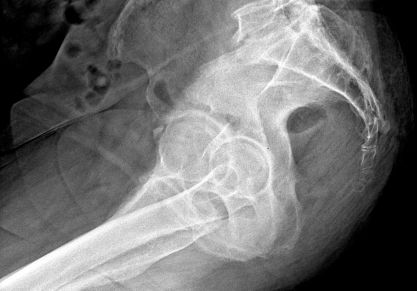

Чем опасно разрушение тазобедренного сустава: признаки и симптомы, тактика лечения

Почему происходит разрушение тазобедренного сустава: причины, стадии, последствия коксартроза. Лечение медикаментами, эндопротезирование ТБС при разрушении.